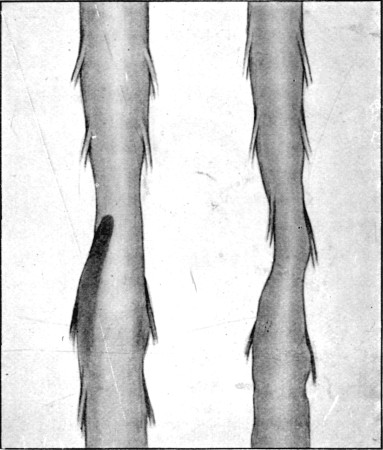

49. Explosive Exit and Entry Wounds of Legs159